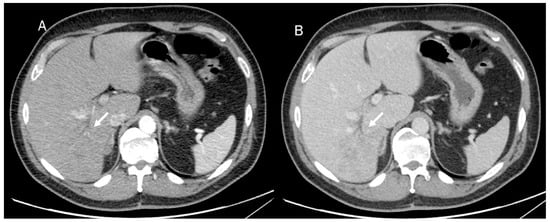

In US studies, mass-forming ICC occurs as a large non-encapsulated mass with lobulated or variable shape. It can also be associated with liver capsule retraction and dilated peripheral bile ducts [80]. With respect to its pathomorphological characteristics (necrosis, fibrosis, and tumor growth), ICC can show a heterogeneous basal-US echogenicity pattern [81]. During CEUS assessment, ICC could show hyperenhancement during the arterial phase (Figure 3) with washout. According to several authors, ICC washout at its earliest stage is comparable to HCC, and this finding should guide a correct diagnosis [82,83,84].

Figure 3.

US and CEUS assessment of ICC: On US (A), the lesion (arrow) shows iso-hypoechoic pattern compared to hepatic parenchymal. During arterial phase (B), the lesion shows arterial hyperenhancement (arrow), with washout (arrow) in portal phase (C).